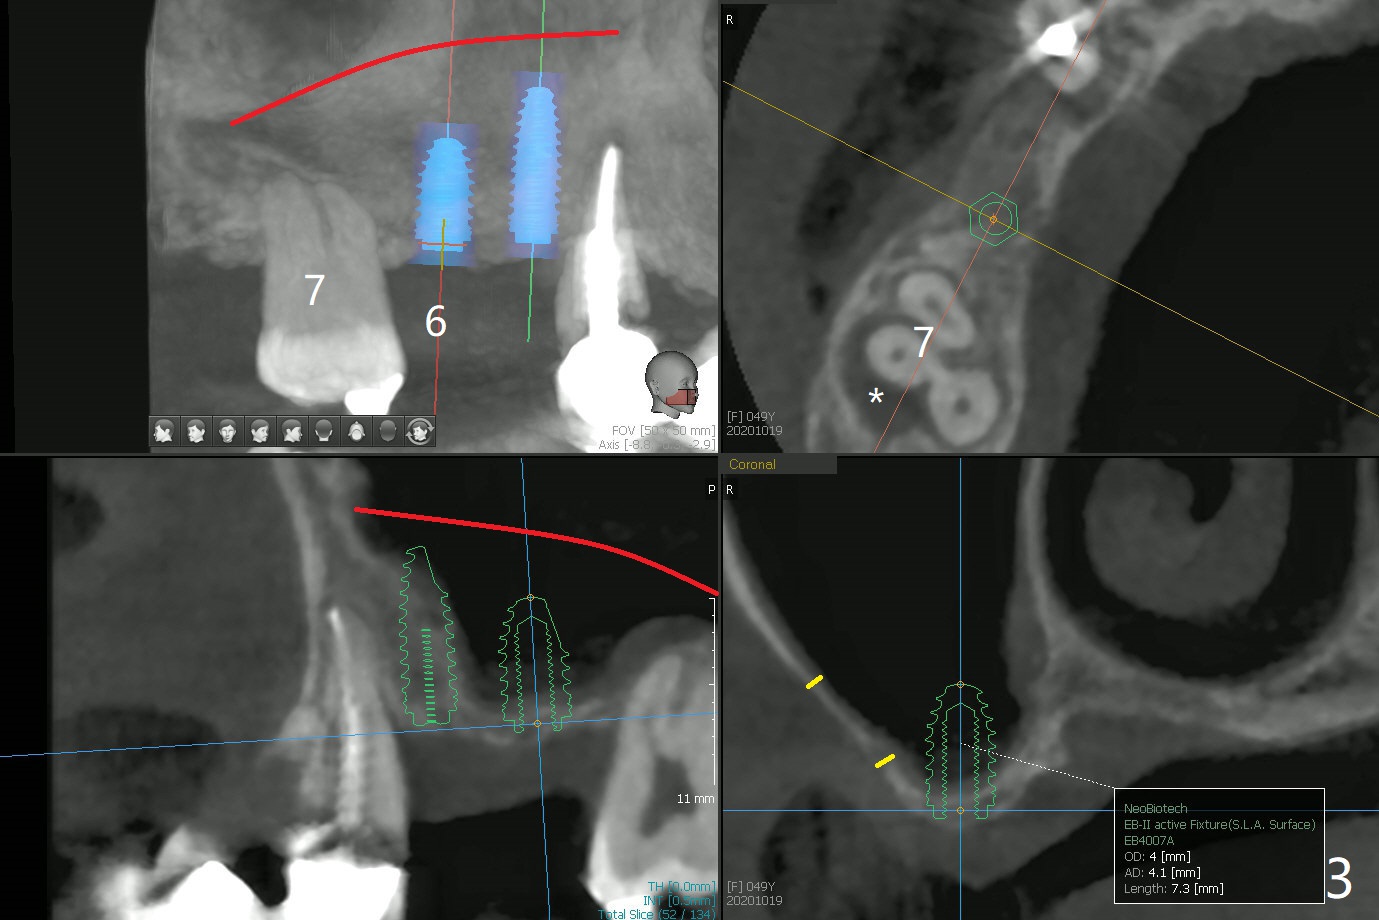

49岁女(图一)同意先做右上5,6种植(图二,三),但是必须先做外提升,高至5根尖(图二:红线),范围延申至右上7,后者骨质吸收厉害(图三:*),预后不佳。后者可能是好几年的事情,是杞人忧天?准备DIO Sinus Master Kit, sinus curettes (curved), a round flat osteotome (in sinus box) and mallet as well as PRFx2。图三黄线代表外提升入口。外提失败因为遇到动脉(图四),上牙槽中血管穿过上颌窦前壁(图五)。实验室建议在右上5种植(图六至八)。结果内提同期种植。